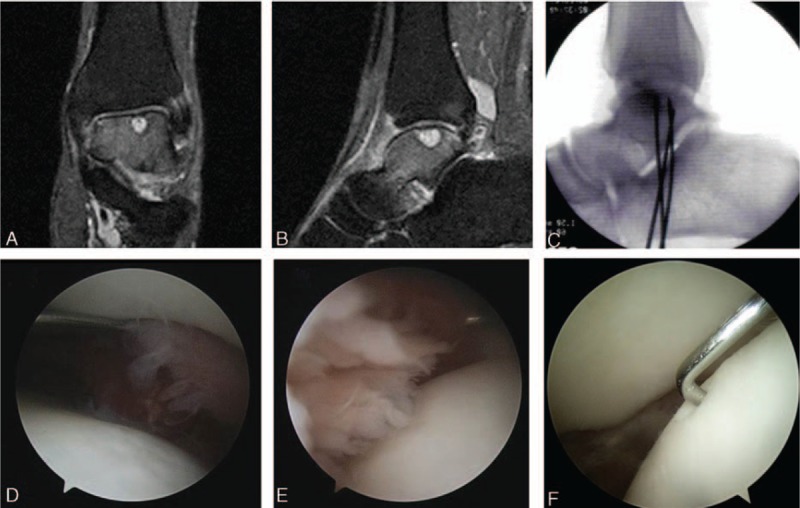

Plain anteroposterior (AP) and lateral radiographs of the left ankle showed a radiolucent lesion at the central portion of the talus. In computed tomography (CT), there was a subchondral cystic lesion (7 × 7 × 10 mm sized) on the central portion of the talus and multiple small subchondral cystic lesions on the medial side of the talus. T2-weighted coronal and sagittal magnetic resonance imaging (MRI) showed bone marrow edema on talus and subchondral cysts with high-signal intensity (Fig. 1A and B). The overlying cartilage on the osteochondral lesion was relatively intact. Based on CT and MRI, we diagnosed it as OLT with subchondral cyst and degenerative arthritis (Anderson stage 2A). Laboratory data showed normal values of white blood cell (WBC), neutrophil, erythrocyte sedimentation rate (ESR), and C-reactive protein (CRP) levels (8700/μL, 5200/μL, and 9 and 0.2 mg/dL, respectively).

Figure 1.

T2-weighted coronal (A) and sagittal (B) magnetic resonance images demonstrating bone marrow edema on talar body and osteochondral lesion with subchondral cyst. Retrograde drilling was performed using K-wires under C-arm image intensifier. (C) Arthroscopic finding showing synovitis surrounding subchondral cyst and relatively intact and stable talar cartilage (D—medial side, E—lateral side, F—central portion).

In arthroscopic findings, there was synovitis surrounding the subchondral cyst in ankle joint (Fig. 1D–F). However, the cartilage on the osteochondral lesion was relatively intact with mild delamination (Fig. 1D–F). We performed arthroscopic synovectomy for nonspecific inflammatory synovium (meniscoid-like lesion). We performed retrograde drilling using K-wires (0.062 inch) for OLT without penetrating the subchondral bone with C-arm image intensifier (Fig. 1C). Pathologist reported the biopsy results of the synovium. It showed hyalinized connective tissue consistent with meniscoid-like lesion.